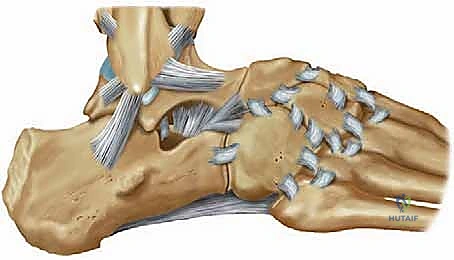

التشريح الدقيق لمفصل الكاحل: لماذا تحدث الإصابة؟

الأربطة الجانبية للكاحل (Lateral Ligament Complex)

تتكون الأربطة الجانبية، وهي الأكثر عرضة للتمزق أثناء التواء الكاحل للداخل (Inversion Sprain)، من ثلاثة أربطة رئيسية:

1. الرباط الكاحلي الشظوي الأمامي (ATFL): هو الرباط الأضعف والأكثر تعرضاً للتمزق. يمنع انزلاق عظمة الكاحل (Talus) للأمام.

2. الرباط العقبي الشظوي (CFL): رباط قوي يشبه الحبل، يربط بين عظمة الشظية وعظمة الكعب. يمنع الميلان المفرط للكاحل.

3. الرباط الكاحلي الشظوي الخلفي (PTFL): هو الأقوى ونادراً ما يتمزق إلا في حالات الخلع الكامل للمفصل.